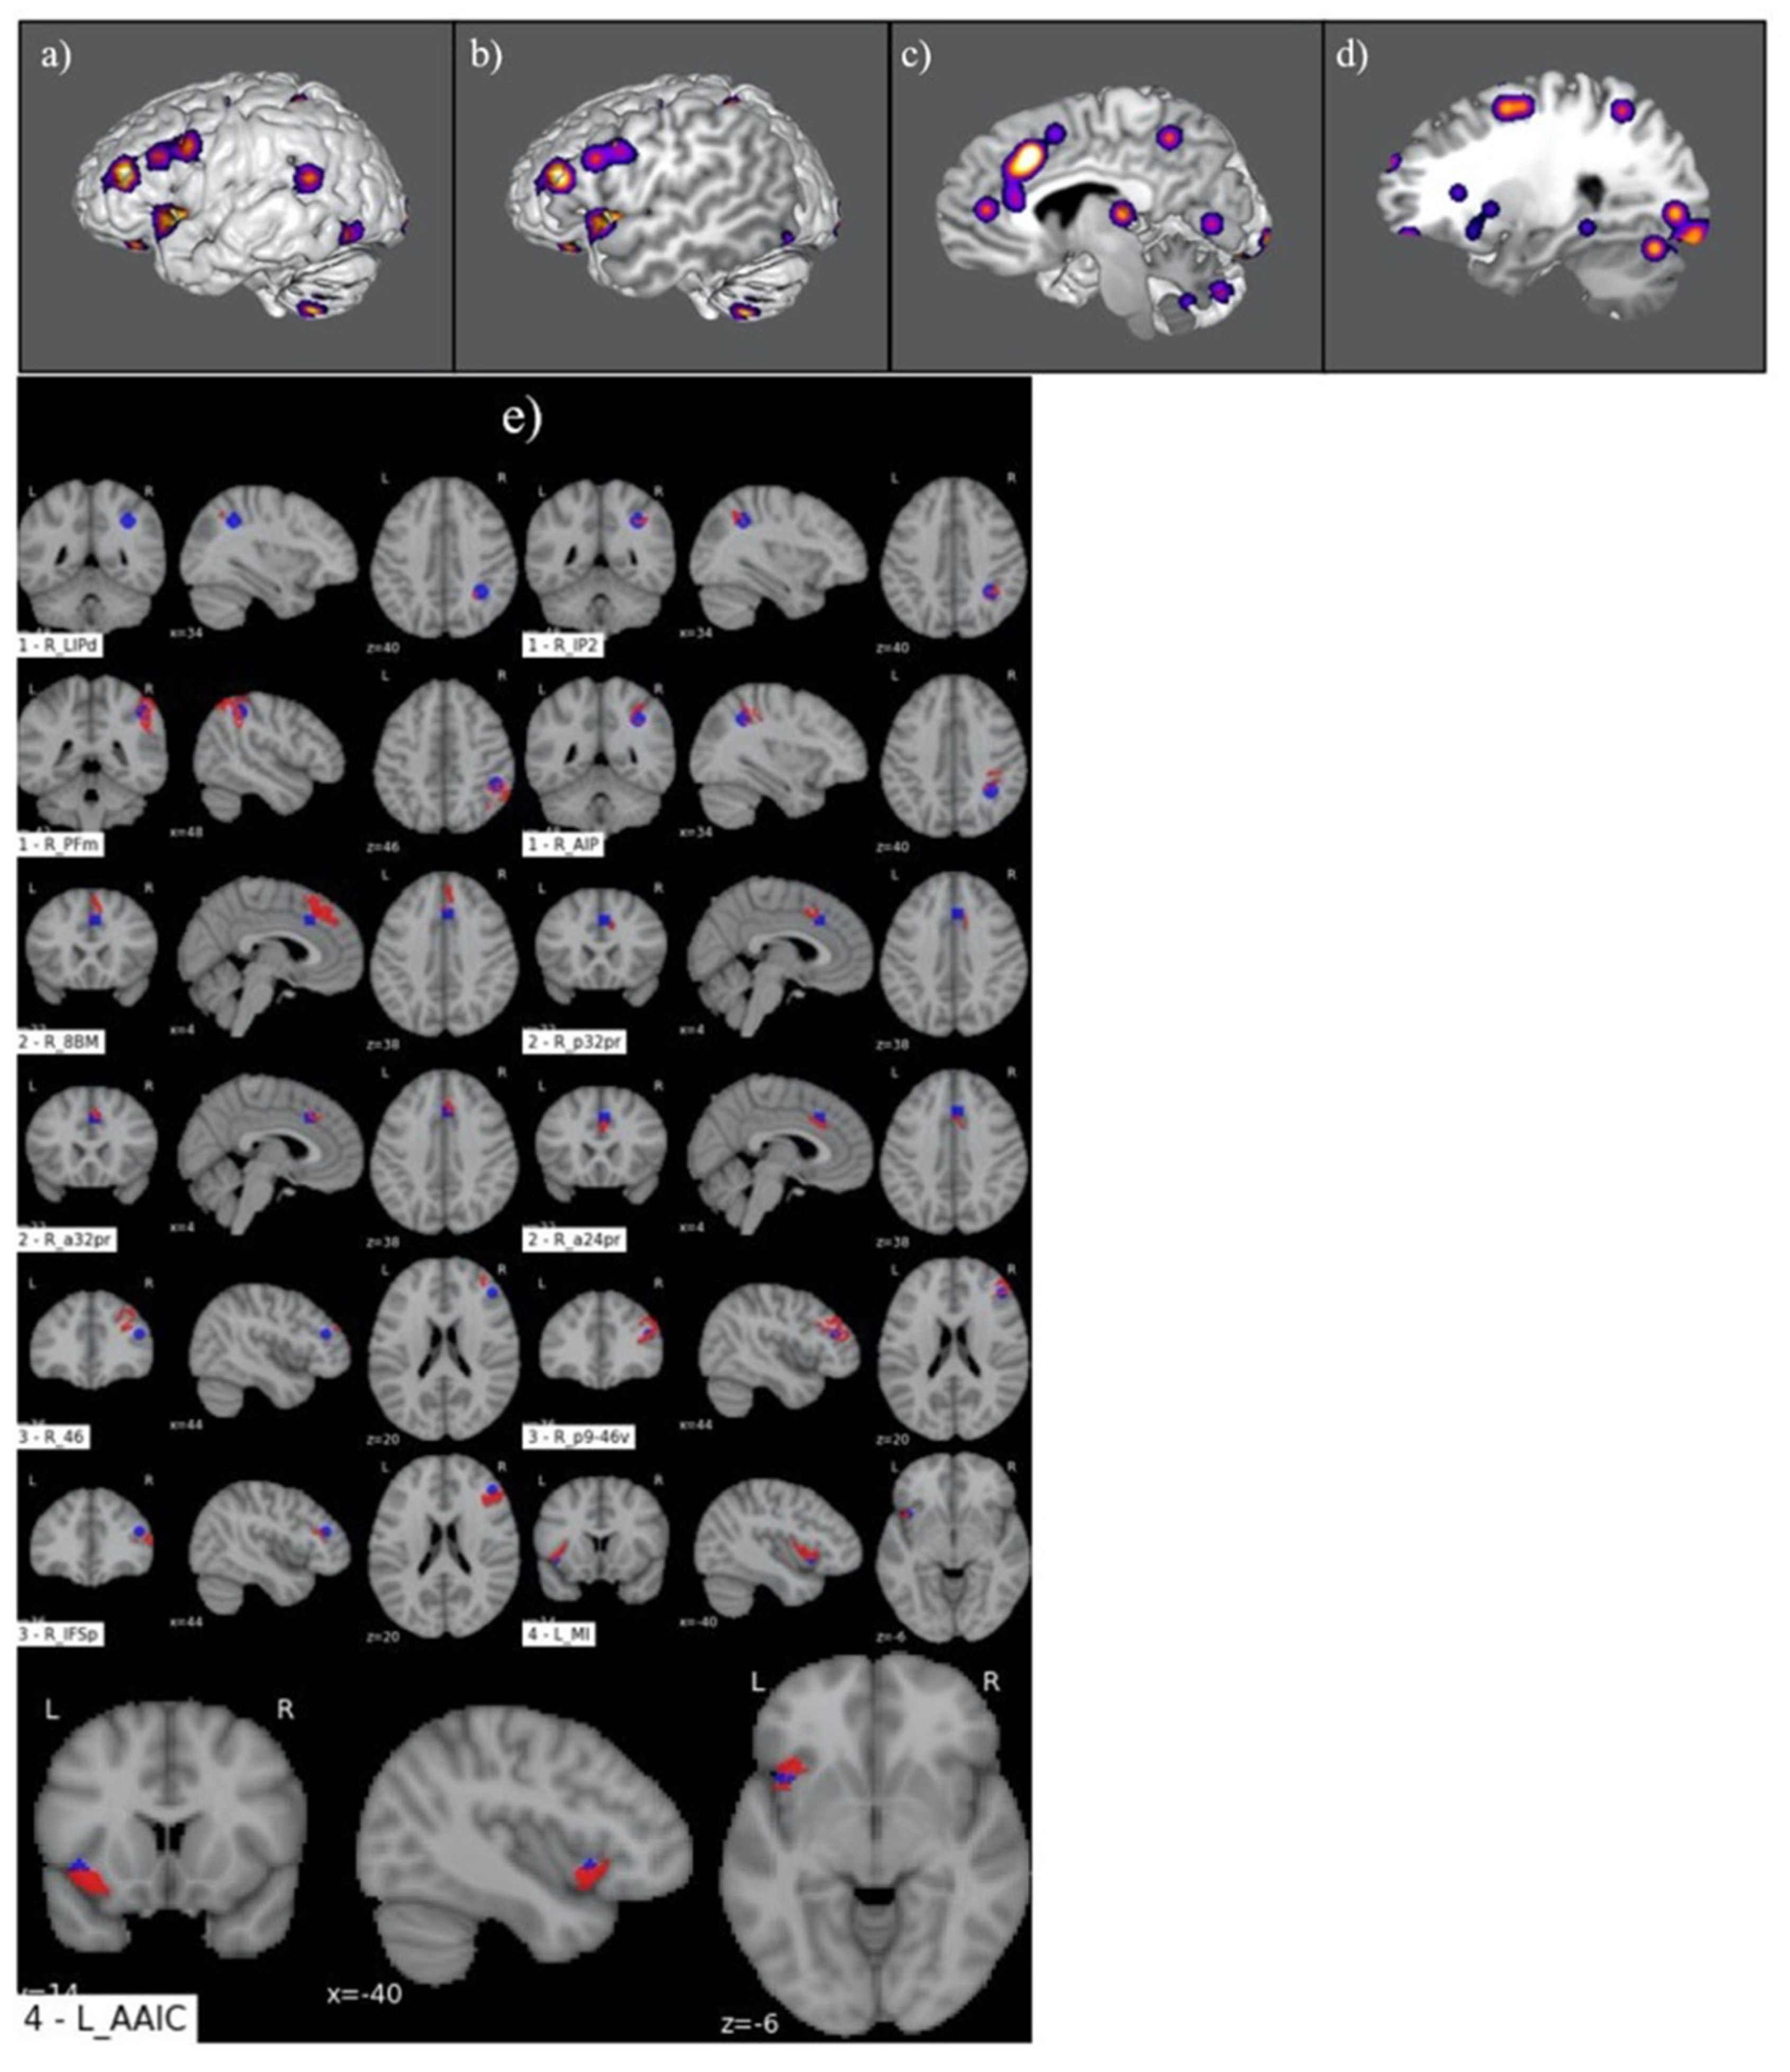

3.1. Judgement Activation Maps

3.2. Parcellation-Based Comparative Analysis